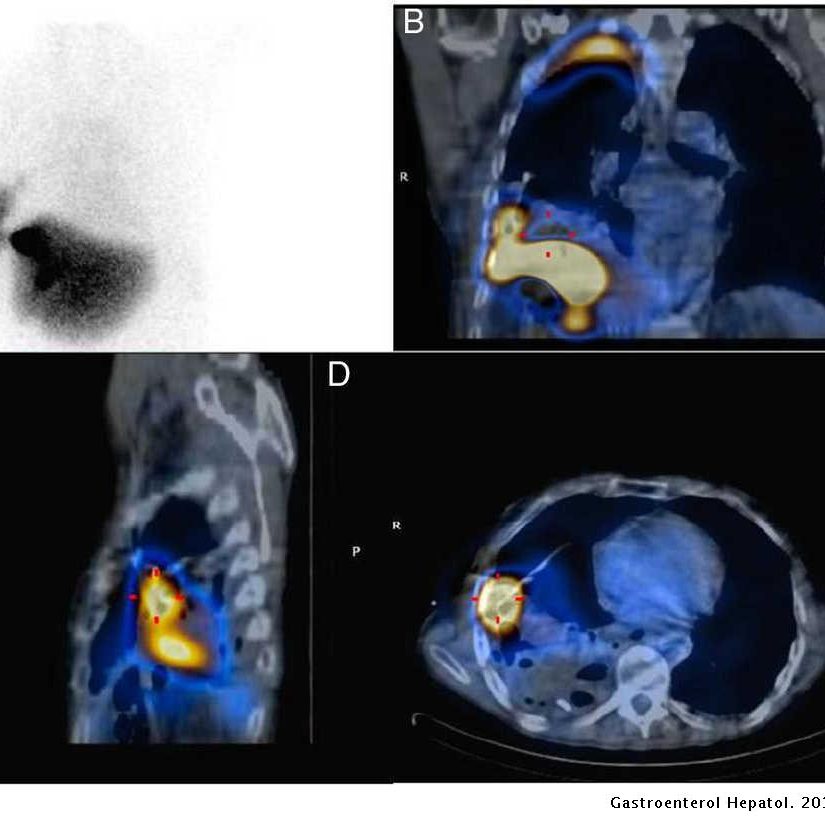

ESTUDIO ISOTÓPICO DE HEMORRAGIAS O SANGRADO DIGESTIVO

La exploración consiste en la inyección intravenosa de un radiofármaco y adquisición de imágenes inmediatamente tras la inyección y después se continuará hasta que se localizase el foco de sangrado.

El tiempo de duración de la exploración varía de forma muy notable de un paciente a otro.